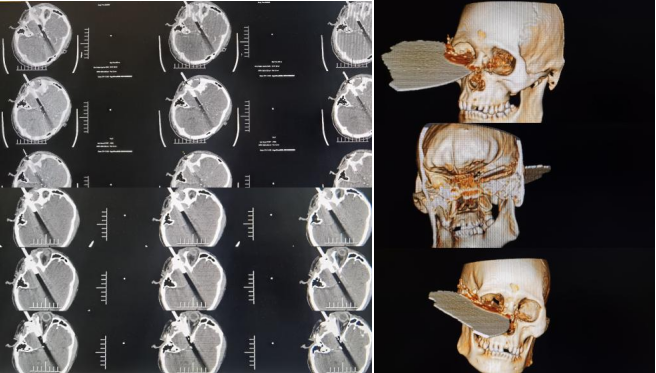

患者入院时烦躁,意识模糊不对答,右侧头面部嵌入断裂切割锯,伤口从右颞经右眼眶底延伸至右鼻根,断裂切割锯一直嵌留于右侧头面部,伤口伴有活动性出血及脑脊液漏,双侧眼睑肿胀,睁眼困难。患者转入神经外科二病区后,科室高度重视,神经外科二病区付登礼教授团队立即组织抢救,初步诊断为开放性颅脑损伤中型、右额颞叶脑挫伤并脑内血肿、创伤性蛛网膜下腔出血、右额颞顶硬膜下血肿、左额颞硬膜下血肿、颅底骨折、颜面部开放性损伤。

时间就是生命,神经外科二病区立即为患者开放绿色通道,迅速指导家属办理入院手续,完成病史采集、体格检查,专人固定患者头部避免异物造成二次伤害,陪同患者完成相关CT扫描三维重建等相关影像学检查,明确患者病情,并组织眼科、耳鼻咽喉科、整形外科等相关科室对该患者进行联合会诊,完善术前准备。

异物刺破患者硬脑膜进入颅内,脑出血、脑组织外漏,有脑脊液流出,大量破碎异物残留于皮下、颞肌及脑组织内。整个手术风险性高、难度大,神经外科二病区张崇进医生在付登礼主任指导下通过显微镜辅助彻底清除脑内血肿,同时清除异物周围挫伤脑组织、残留异物碎片及受污染脑组织,沿异物周围仔细探查。眼科医生沿异物刺入处皮肤向眶内进行探查,耳鼻咽喉科医生配合探查鼻腔,确认无大血管受损,张崇进医生再次确认颅内血管与异物无粘连,完整取出嵌入异物,异物取出后未见活动性出血。显微镜下沿异物入颅处再次仔细探查,未见活动性出血。